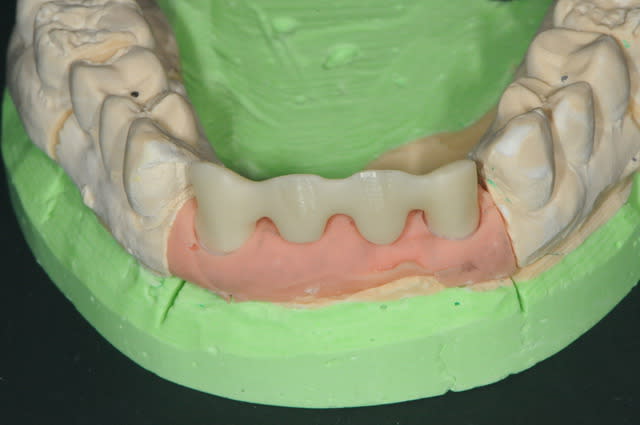

la prothèse immédiate grâce aux empreintes de départ.

ici la résine c'est du protemp 4, c'est super mais un peu gras.